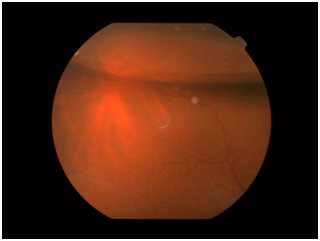

The patient was immediately referred to a vitreoretinal consultant, who noted the vitreous was haze. B-scan ultrasound showed vitreous cells without retinal detachment. Probable acute bacterial endophthalmitis was diagnosed. Twenty-three gauge-three port Pars plana vitrectomy (PPV) system was performed. Aqueous and vitreous samples were taken before opening the infusion cannula. Core vitrectomy was done. Intravitreal injection of vancomycin and ceftazidime in standard doses was injected at the end of PPV procedure. Aqueous and vitreous samples were sent for Gram stain, aerobic and anaerobic cultures. Gram stain of the aqueous revealed a few white blood cells showed no organisms. Aqueous cultures were negative. Vitreous Gram stain showed white blood cells and gram-positive cocci, and vitreous cultures grew coagulase-negative Staphylococcus epidermidis. The symptoms and inflammation improved rapidly over the next several days. The gatifloxacin eye drops were continued for 2 weeks, and the prednisolone eye drops were tapered over the following month. One month after PPV, the UCVA was 20/25. Three Months later, he presented to the clinic complaining of blurred vision of the same eye. His vision was hand motion of the right eye. Anterior segment examination was unremarkable with ICL in place. Fundus exam showed retinal detachment involving the macula with super temporal break. The patient was admitted for PPV, endolaser and gas injection (C3F8). Postoperatively, there was no anterior segment inflammation and the retina was flat under the gas (Figure 2) (Figure 3). At the most recent visit, the UCVA was 20/30 with stable ICL and quiet eye.

Figure 3 Fundus photograph showing flat retina and the remaining gas after PPV for retinal detachment.